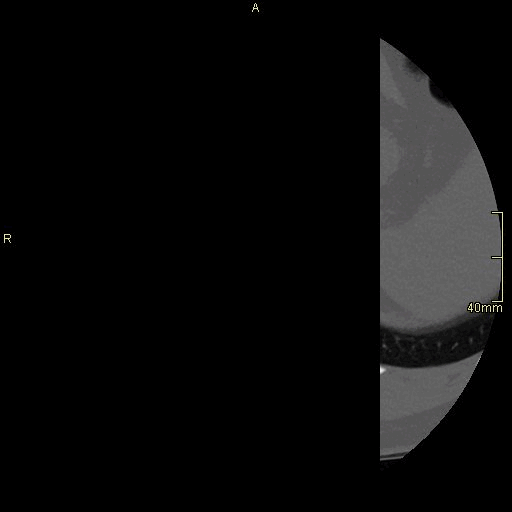

CT Lumbosacral Spine Non Contrast- Bone window (axial)